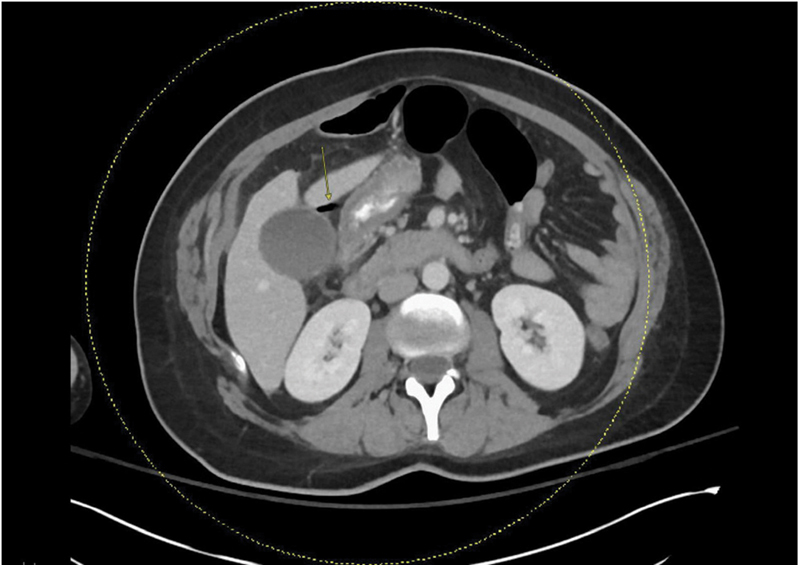

Peptic ulcers and complications, such as perforation, are rare during pregnancy and the puerperium. Accordingly, many clinicians may place these diagnoses low on their differential diagnosis. We present two case reports of primigravida, advanced maternal-age females with a history of irritable bowel syndrome and nonsteroidal anti-inflammatory drug use found to have perforated duodenal ulcers after cesarean section. Postpartum surgical abdomens may not present with classic guarding and rigidity. A low threshold for imaging and identification of risk factors is critical to timely diagnosis and management.

Abstract Image